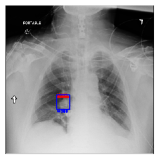

CXR8 [21] is one of the most commonly accessible radio-logical examination for many lung diseases. The data consists of 112,120 images collected by 30,805 patients. As shown in Table I, nine class labels of normal state and eight diseases including cancer are defined for classification. The data is divided into training set and test set, and the classification accuracy and ROC curve with several well-known deep network such as VGG16, GoogLeNet, and ResNet, are reported on the original paper [21]. In addition, 984 Bounding Boxes (B-Box) are provided for localization. Fig. 5 shows image examples of CXR8. The red rectangle in the image shows given B-Box.

IV-D Investigation of the generated heatmap

By using the training result of the Adaptive DBN, the heatmap images were generated in addition to detection of B-Box. The heatmaps in Fig. 10 to Fig. 14 show the detection result of B-Box and the generated heatmap for some images. The red and blue rectangles in the image are given B-Box and detected B-Box, respectively. A heatmap is represented by the continuous value of range , where the color map is jet color array (red means high value, while blue means small value). The diseases for detected B-Boxes in Fig. 10 to Fig. 14 were as follows; Infiltration (Fig. 10), Mass (Fig. 10), Nodule (Fig. 10), Mass and Pneumothorax (Fig. 10), Atelectasis (Fig. 14), Infiltration (Fig. 14), Atelectasis (Fig. 14), Atelectasis (Fig. 14).

Overall, the red area of the generated heatmap included in both the given B-Box and detected B-Box. On the other hand, the blue or yellow areas didn’t include in these B-Boxes. This tendency was seen in not only large diseases (e.g. Cardiomegaly or Infiltration) such as Fig. 10, but also small diseases (e.g. Mass or Nodule) such as Fig. 10. We consider that the experimental results caused by the discrete heatmap with binary output of final RBM layer instead of continuous heatmap. As a result, the red regions represents localization with strong relation to diseases and blue regions represents localization with weak relation. The generated heatmap shows the portion with strong relation more clearly.

In Fig. 14, the detected B-Box was located at a little upper than the given B-Box. The red area of the heatmap was also at upper position. The detected B-Box is slightly larger than the given B-Box. The detected B-Boxes are almost same as the given B-Boxes except the different size. For better detection capability, the feature of the generated heatmap will be investigated with the medical specialists.